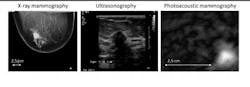

The device is built into a hospital bed, where the patient lies prone and positions her breast for imaging. Laser light at a wavelength of 1064 nm scans the breast. Because there is increased absorption of the light in malignant tissue the temperature slightly increases. With the rise in temperature, thermal expansion creates a pressure wave, which is detected by an ultrasound detector placed on one side of the breast. The resulting photoacoustic signals are then processed by the PAM system and reconstructed into images. These images reveal abnormal areas of high intensity (tumor tissue) as compared to areas of low intensity (benign tissue). This is one of the first times that the technique has been tested on breast-cancer patients.

By comparing the photoacoustic data with conventional diagnostic X-rays, ultrasound imaging, MRI, and tissue exams, the researchers showed that malignancies produced a distinct photoacoustic signal that is potentially clinically useful for making a diagnosis of breast cancer. The team also observed that the photoacoustic contrast of the malignant tissue is higher than the contrast provided by the conventional X-ray mammographies.